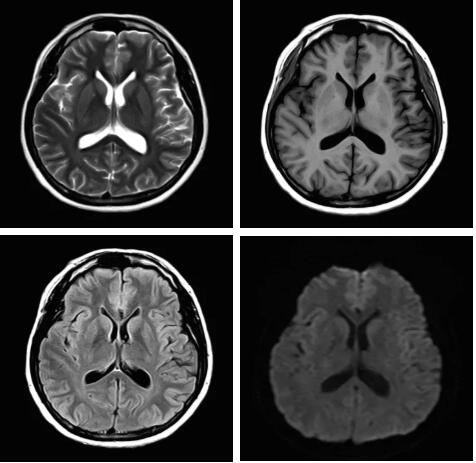

見所未見 微小腫瘤無處遁藏——

“螢火蟲”成像技術 顱內腫瘤微小病灶檢出新發(fā)現(xiàn)

此技術主要用于神經系統(tǒng)惡性腫瘤,以及其他腫瘤腦轉移瘤篩查。傳統(tǒng)情況下做腫瘤腦轉移篩查,很容易漏掉5mm以下小病灶,臨床發(fā)現(xiàn)后干預治療比較晚,要實現(xiàn)2mm高空間分辨率和超薄層全腦掃描在保證信噪比的情況下需要很長時間大概十多分鐘,而且薄層增強序列顱內血管呈高亮信號,會干擾顱內小病灶的觀察,血管和小病灶區(qū)分困難。佳能”螢火蟲”成像技術既可以實現(xiàn)高空間分辨率和超薄層(最薄可實現(xiàn)0.2mm)全腦掃描,掃描時間短,2-3分鐘即可實現(xiàn)全腦3D掃描,同時避免了血管高亮信號的干擾,對顱內原發(fā)或繼發(fā)的微小腫瘤檢查有重大意義。“螢火蟲”成像技術具有磁敏感效應,對于亞急性血敏感敏感,可以區(qū)分出血和強化的腫瘤。